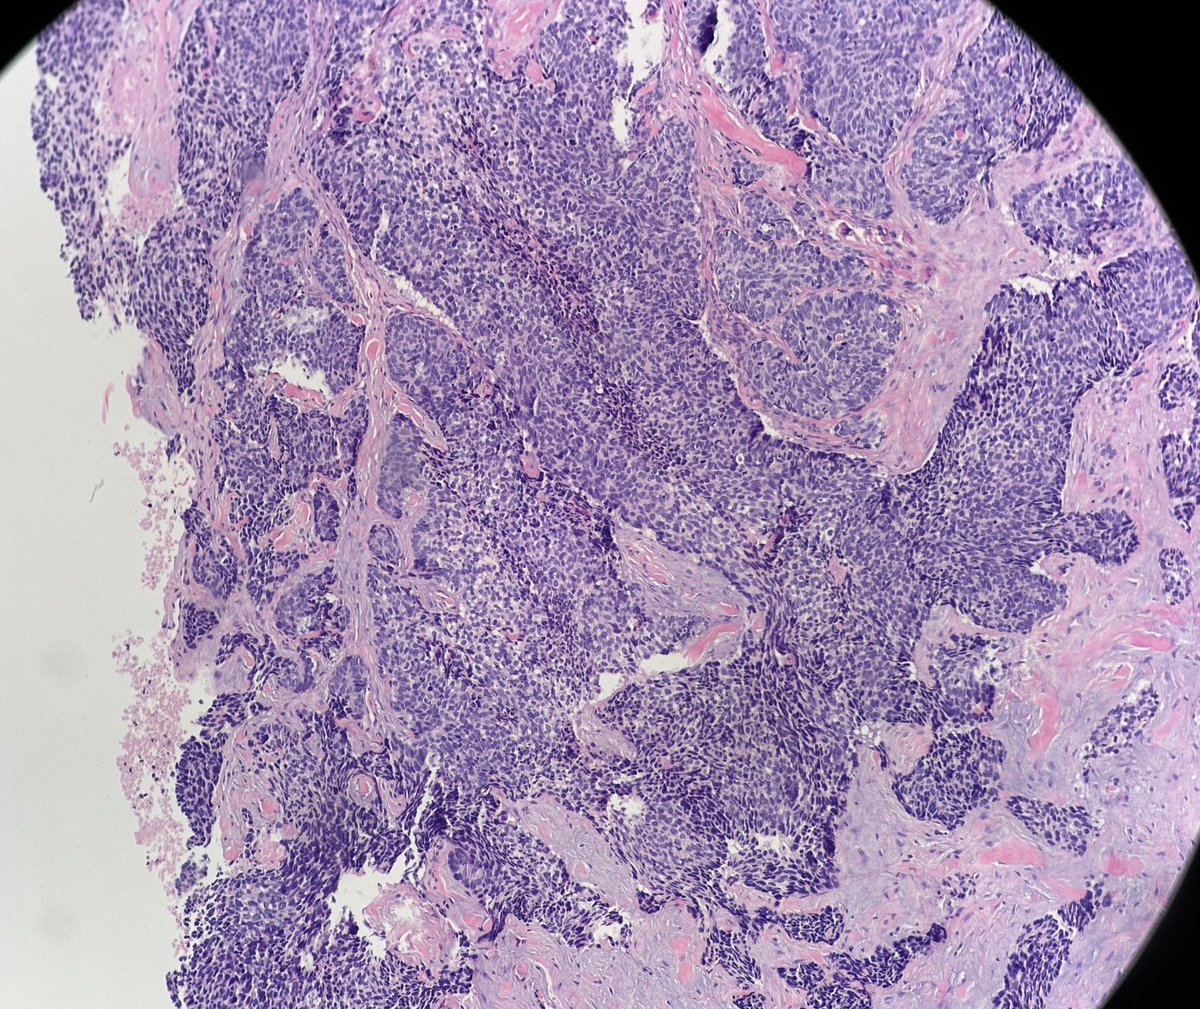

65 year old man posterior auricular neck deep dermal nodule. easy peezy?#dermpath #PathTwitter #dermatology Etan Marks, DO @ArjunRamaiya1 Lorand Kis Olaleke Folaranmi Tristan Rutland MBBS FRCPA IFCAP Trish Stratus Marcelasaeblima. Allison Osmond MD MSc FRCPC Ahmed Alomari, MD Gonzalo De Toro